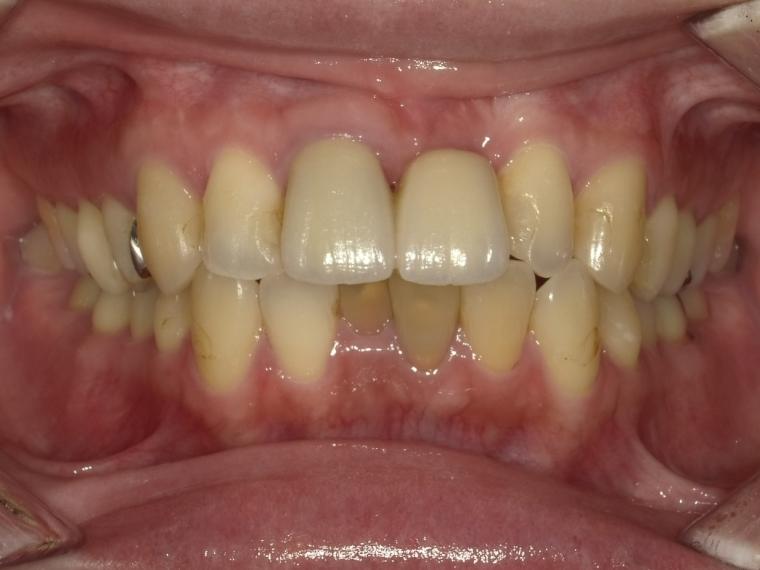

AFTER

37歳女性/上1本欠損/インプラント埋込手術

抜歯後に土台となる骨を作る処置の後、インプラントを1本埋入しました。

現在も定期検診で拝見させていただいています。